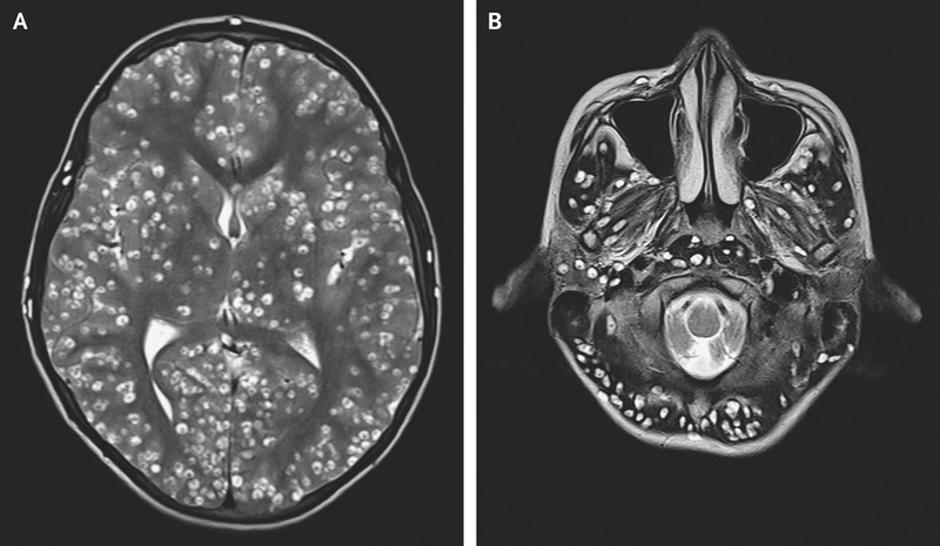

Magnetna resonanca možganov je pokazala na ciste po vseh delih možganov ( na slikaj spodaj kot bele pike). Okusen obrok svinjskega mesa je v njegovem črevesju spodbudil razvoj trakulje, ki je potovala vse do njenih možganov. Tam je odložila svoje ličinke, zaradi katerih pa so njegovo glavo dobesedno preplavile ogromne ciste.

Fant je trpel za hudo obliko nevrocisticerkoze, eno izmed parazitskih bolezni, ki jo pri človeku povzročajo ličinke svinjske trakulje. Je najpogostejša parazitska okužba osrednjega živčevja in je lahko tudi glavni vzrok epilepsije. Ljudje s okužijo zaradi jajčec svinjske trakulje v ne dovolj kuhani svinjini in v hrani kontaminirani s človeškim urinom ali iztrebki.